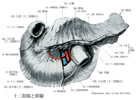

実習人体解剖図譜(浦 良治)

小解剖学図譜